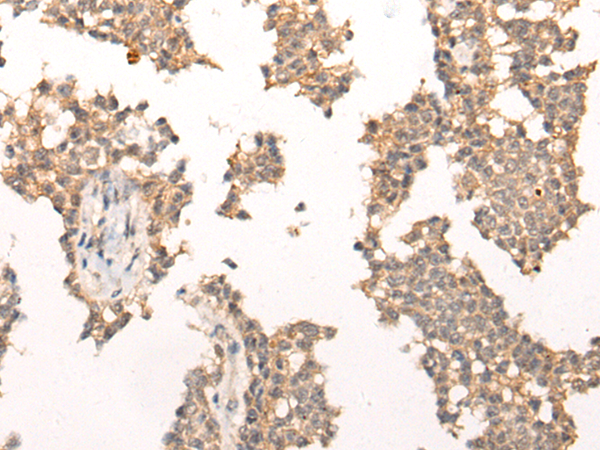

- The image is immunohistochemistry of paraffin-embedded Human liver cancer tissue using P11488(PIAS3 Antibody) at dilution 1/40. (Original magnification: ×200)

- The image is immunohistochemistry of paraffin-embedded Human ovarian cancer tissue using P11488(PIAS3 Antibody) at dilution 1/40. (Original magnification: ×200)